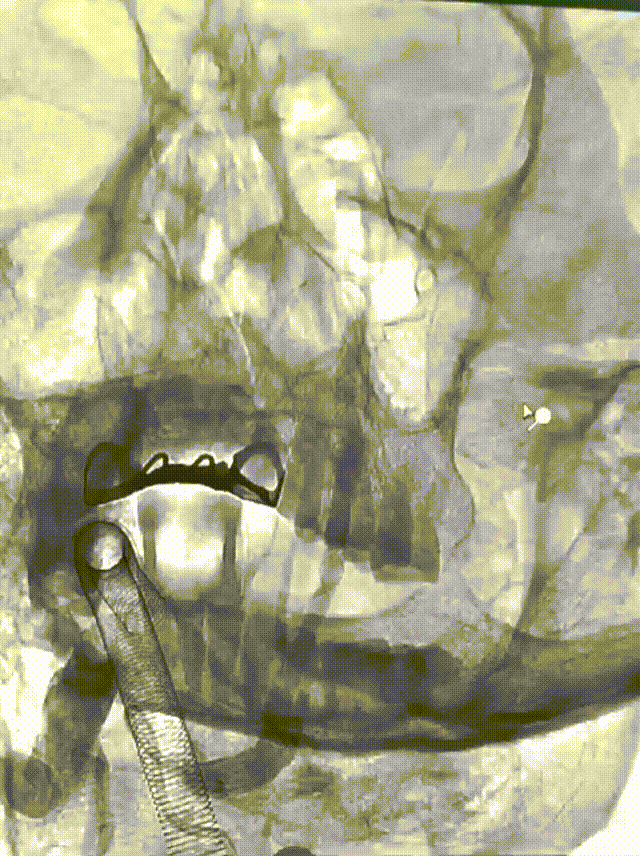

将EasyRadial™输送导管撤至近端V2段动脉瘤处,释放7.0*40mm 血管支架。

血管支架释放完毕造影,手术结束。

EasyRadial™输送导管专为经桡动脉入路手术设计,其凭借出色的支撑力和抗折性能,即使在迂曲复杂的桡动脉路径中,也能轻松应对。该导管通过性好,通路建立顺利,能到达V3-V4段,椎开口大锐角表现优秀没有出现弯折,7F型号可匹配5F中间管和7F薄壁桡鞘。